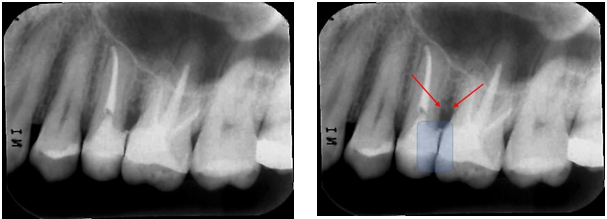

Figure 1 Interproximal radiography of the Molares D region, diagnosed on panoramic radiography. The arrow points to the distal of tooth 16, showing excess of the prosthetic crown, that causes iatrogeny.

Figure 2Periapical radiography of the lower molars D region, diagnosed on panoramic radiography. The yellow arrows point to the distal of tooth 45 and mesial of tooth 47, showing a gross excess of amalgam restorations, which characterize iatrogeny. The red arrows point to the resorption of the alveolar bone crest, due to iatrogenesis. Note that tooth 46 is absent, with teeth 45 and 47 tilted in that space.